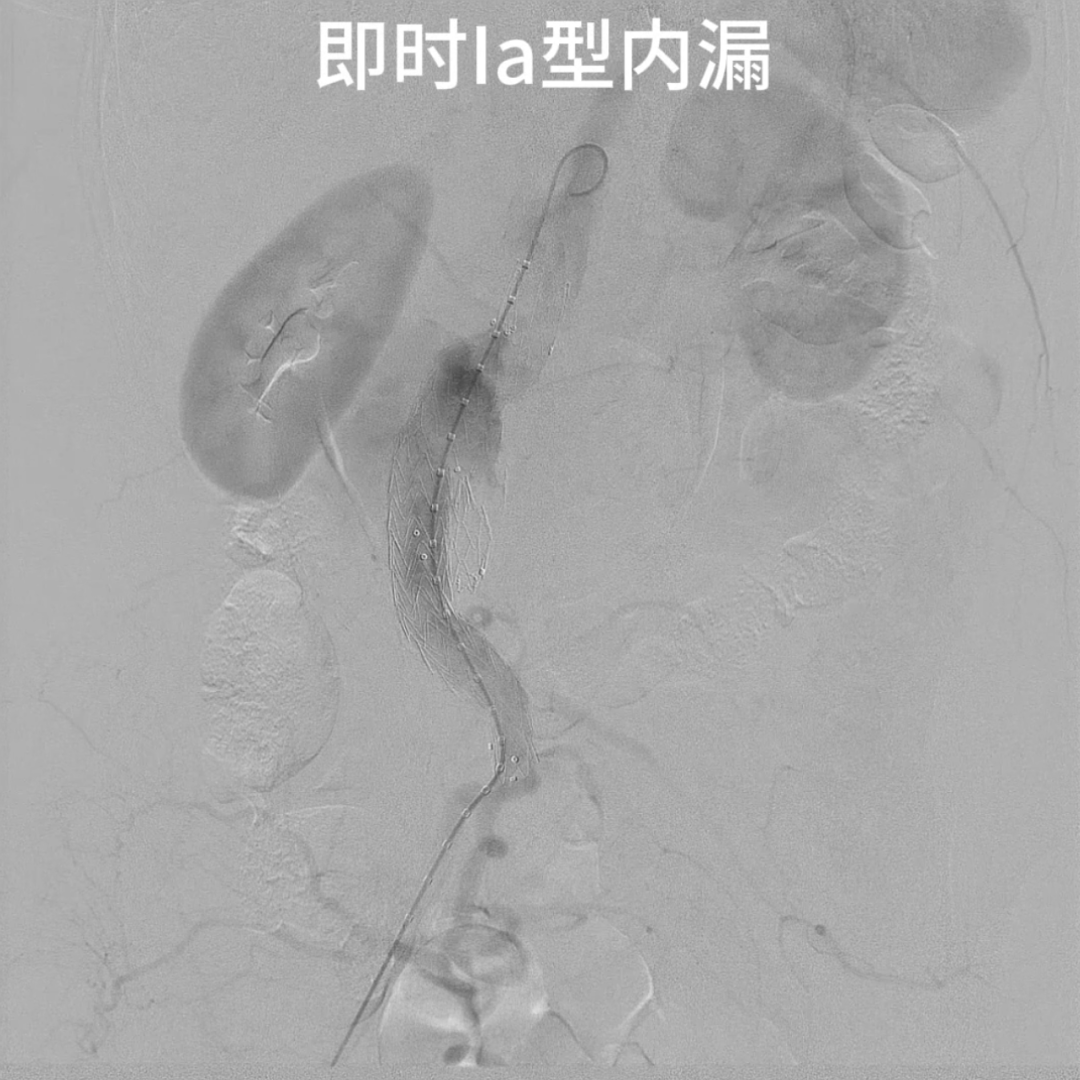

2. 内漏处理

支架释放后出现近端Ⅰ型内漏,原因为瘤颈短、成角大导致支架贴附不充分。经左侧股动脉入路超选至瘤颈近端,以弹簧圈填充瘤颈间隙,造影显示内漏显著减少,达到临床可接受标准。